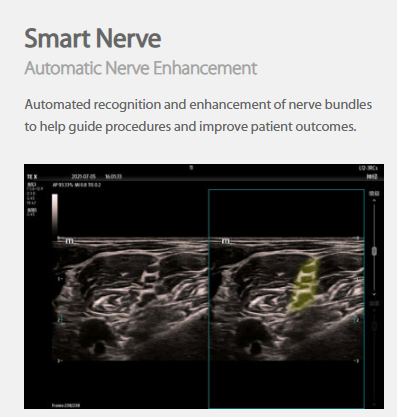

The technology-rich TE X Ultrasound System gives clinicians access to market-leading artificial intelligence (AI)-powered Smart Tools, an ergonomically designed system, and proprietary software-based beamformer Zone Sonography Technology+ (ZST+). By incorporating these elements, the TE X Ultrasound System provides access to advanced diagnostic data, the ability to adapt to the various clinical scenarios at point of care, and best-in-class imaging to help them provide a higher standard of care.